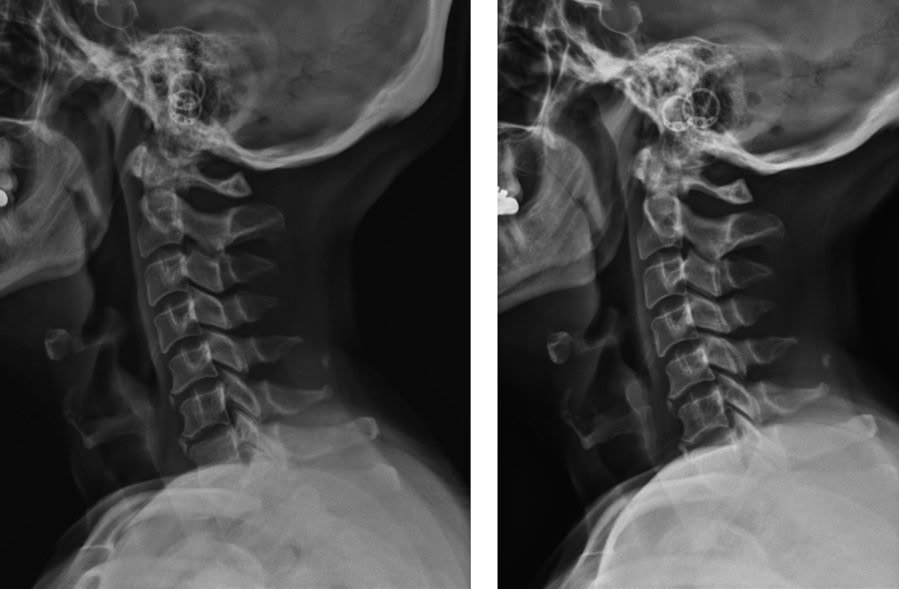

Pre & Post Scan